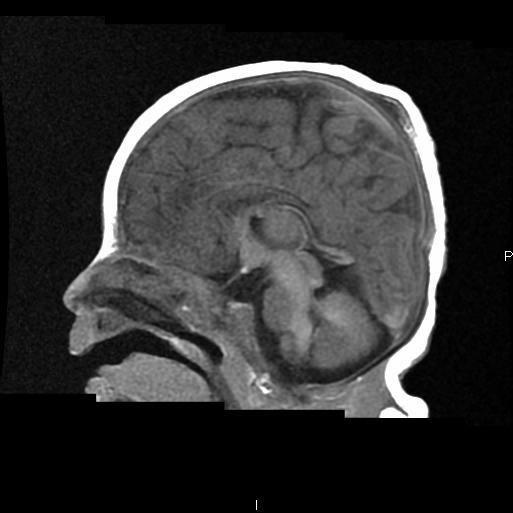

Sweep the Midline:

“Comma shaped Corpus Callosum with abnormal mid body…”

Syntelencephaly: Midline CC “lack of cleavage”

Middle Interhemispheric “MIH” Variant of Holoprosencephaly